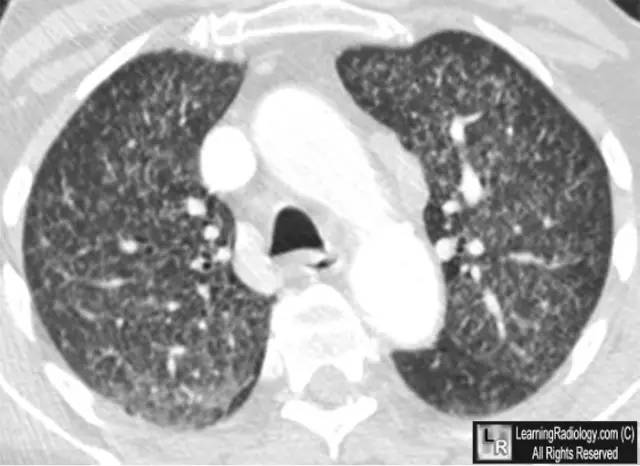

胸部CT轴位扫描

上图:两肺弥漫性粟粒结节

下图:局部特写图(白圆圈内)